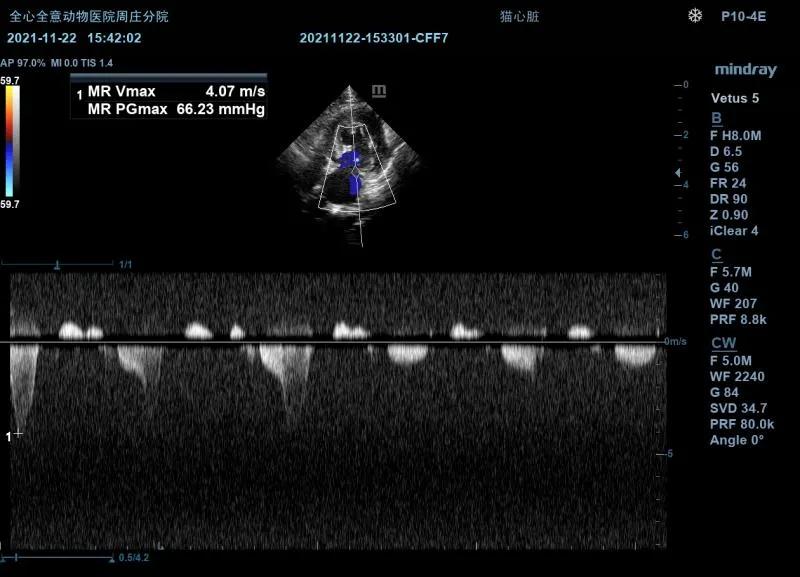

左侧心尖四腔(color):

可见收缩期二间瓣反流信号。

MR Vmax:4.07m/s

左侧测量瓣膜口流速正常。